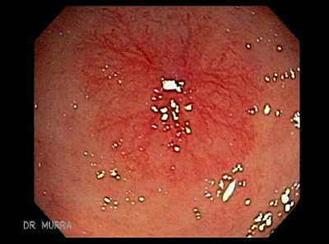

Es una infección del endocardio de las válvulas (superficie anterior).

Válvula nativa:

Endocarditis aguda causa más frecuente estafilococo aureus (estafilococo dorado) suele afectar a las válvulas sanas por lo general, fatal en 6 semanas si no se trata

Endocarditis subaguda causa más frecuente estreptococos del grupo viridans válvulas nativas dañadas previamente causa común de después de procedimientos dentales

El flujo turbulento daña el endotelio de las válvulas activando la hemostasia y se forman vegetaciones asépticas formadas por plaquetas y fibrina (trombo estéril). Luego, estas se contaminan debido a una bacteriemia por un foco séptico, formándose una verruga bacteriana (vegetación séptica), la cual puede destruir la válvula (rotura de cuerdas tendinosas, músculo papilar) y formar abscesos, produciendo la clínica cardiaca; los émbolos sépticos que pasan a la circulación sistémica dan lugar a la clínica extracardiaca (en casos de ADVP, predominan los émbolos pulmonares).

La triada clínica es fiebre (95 %), soplo de regurgitación (85 %) y esplenomegalia (30 %) . Además, podría haber clínica extracardiaca producto de los émbolos sépticos al territorio de la arteria cerebral media, como hemiparesia por un ictus isquémico en pacientes jóvenes o manifestaciones embólicas pulmonares (tos, disnea y hemoptisis), que son más frecuentes en los pacientes ADVP.

Fenómenos embólicos: aneurismas micóticos (10 %), hemorragias conjuntivales, hemorragias “en astilla” en el lecho subungueal las lesiones de Janeway (indoloras, rojizas, en palmas y plantas).

Fenómenos inmunológicos: factor reumatoide positivo, nódulos de Osler (dolorosos, aparecen en los pulpejos y las manchas de Roth en el fondo de ojo).